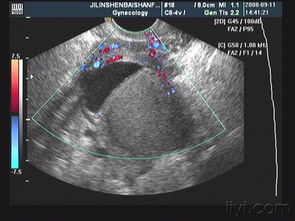

宮頸囊腫是女性常見的一種宮頸慢性炎性反應(yīng),很多女性存在宮頸囊腫,一般沒有特殊的臨床癥狀,所以不需要有特殊的注意事項(xiàng),只需要定期觀察即可。

如果存在明顯的宮頸囊腫,而又出現(xiàn)了一些特殊的臨床癥狀,例如接觸性出血等情況,可能需要進(jìn)行一些物理治療。但大多數(shù)患者是沒有臨床癥狀的,僅僅是通過婦科內(nèi)診,或者是超聲發(fā)現(xiàn)了宮頸囊腫,所以也沒有特殊的注意事項(xiàng),也不用去特殊的治療宮頸囊腫,因?yàn)樗且环N正常的生理現(xiàn)象。

但是對(duì)于宮頸有囊腫的患者,建議一定要進(jìn)行宮頸癌的篩查,除外宮頸癌前病變和宮頸癌。